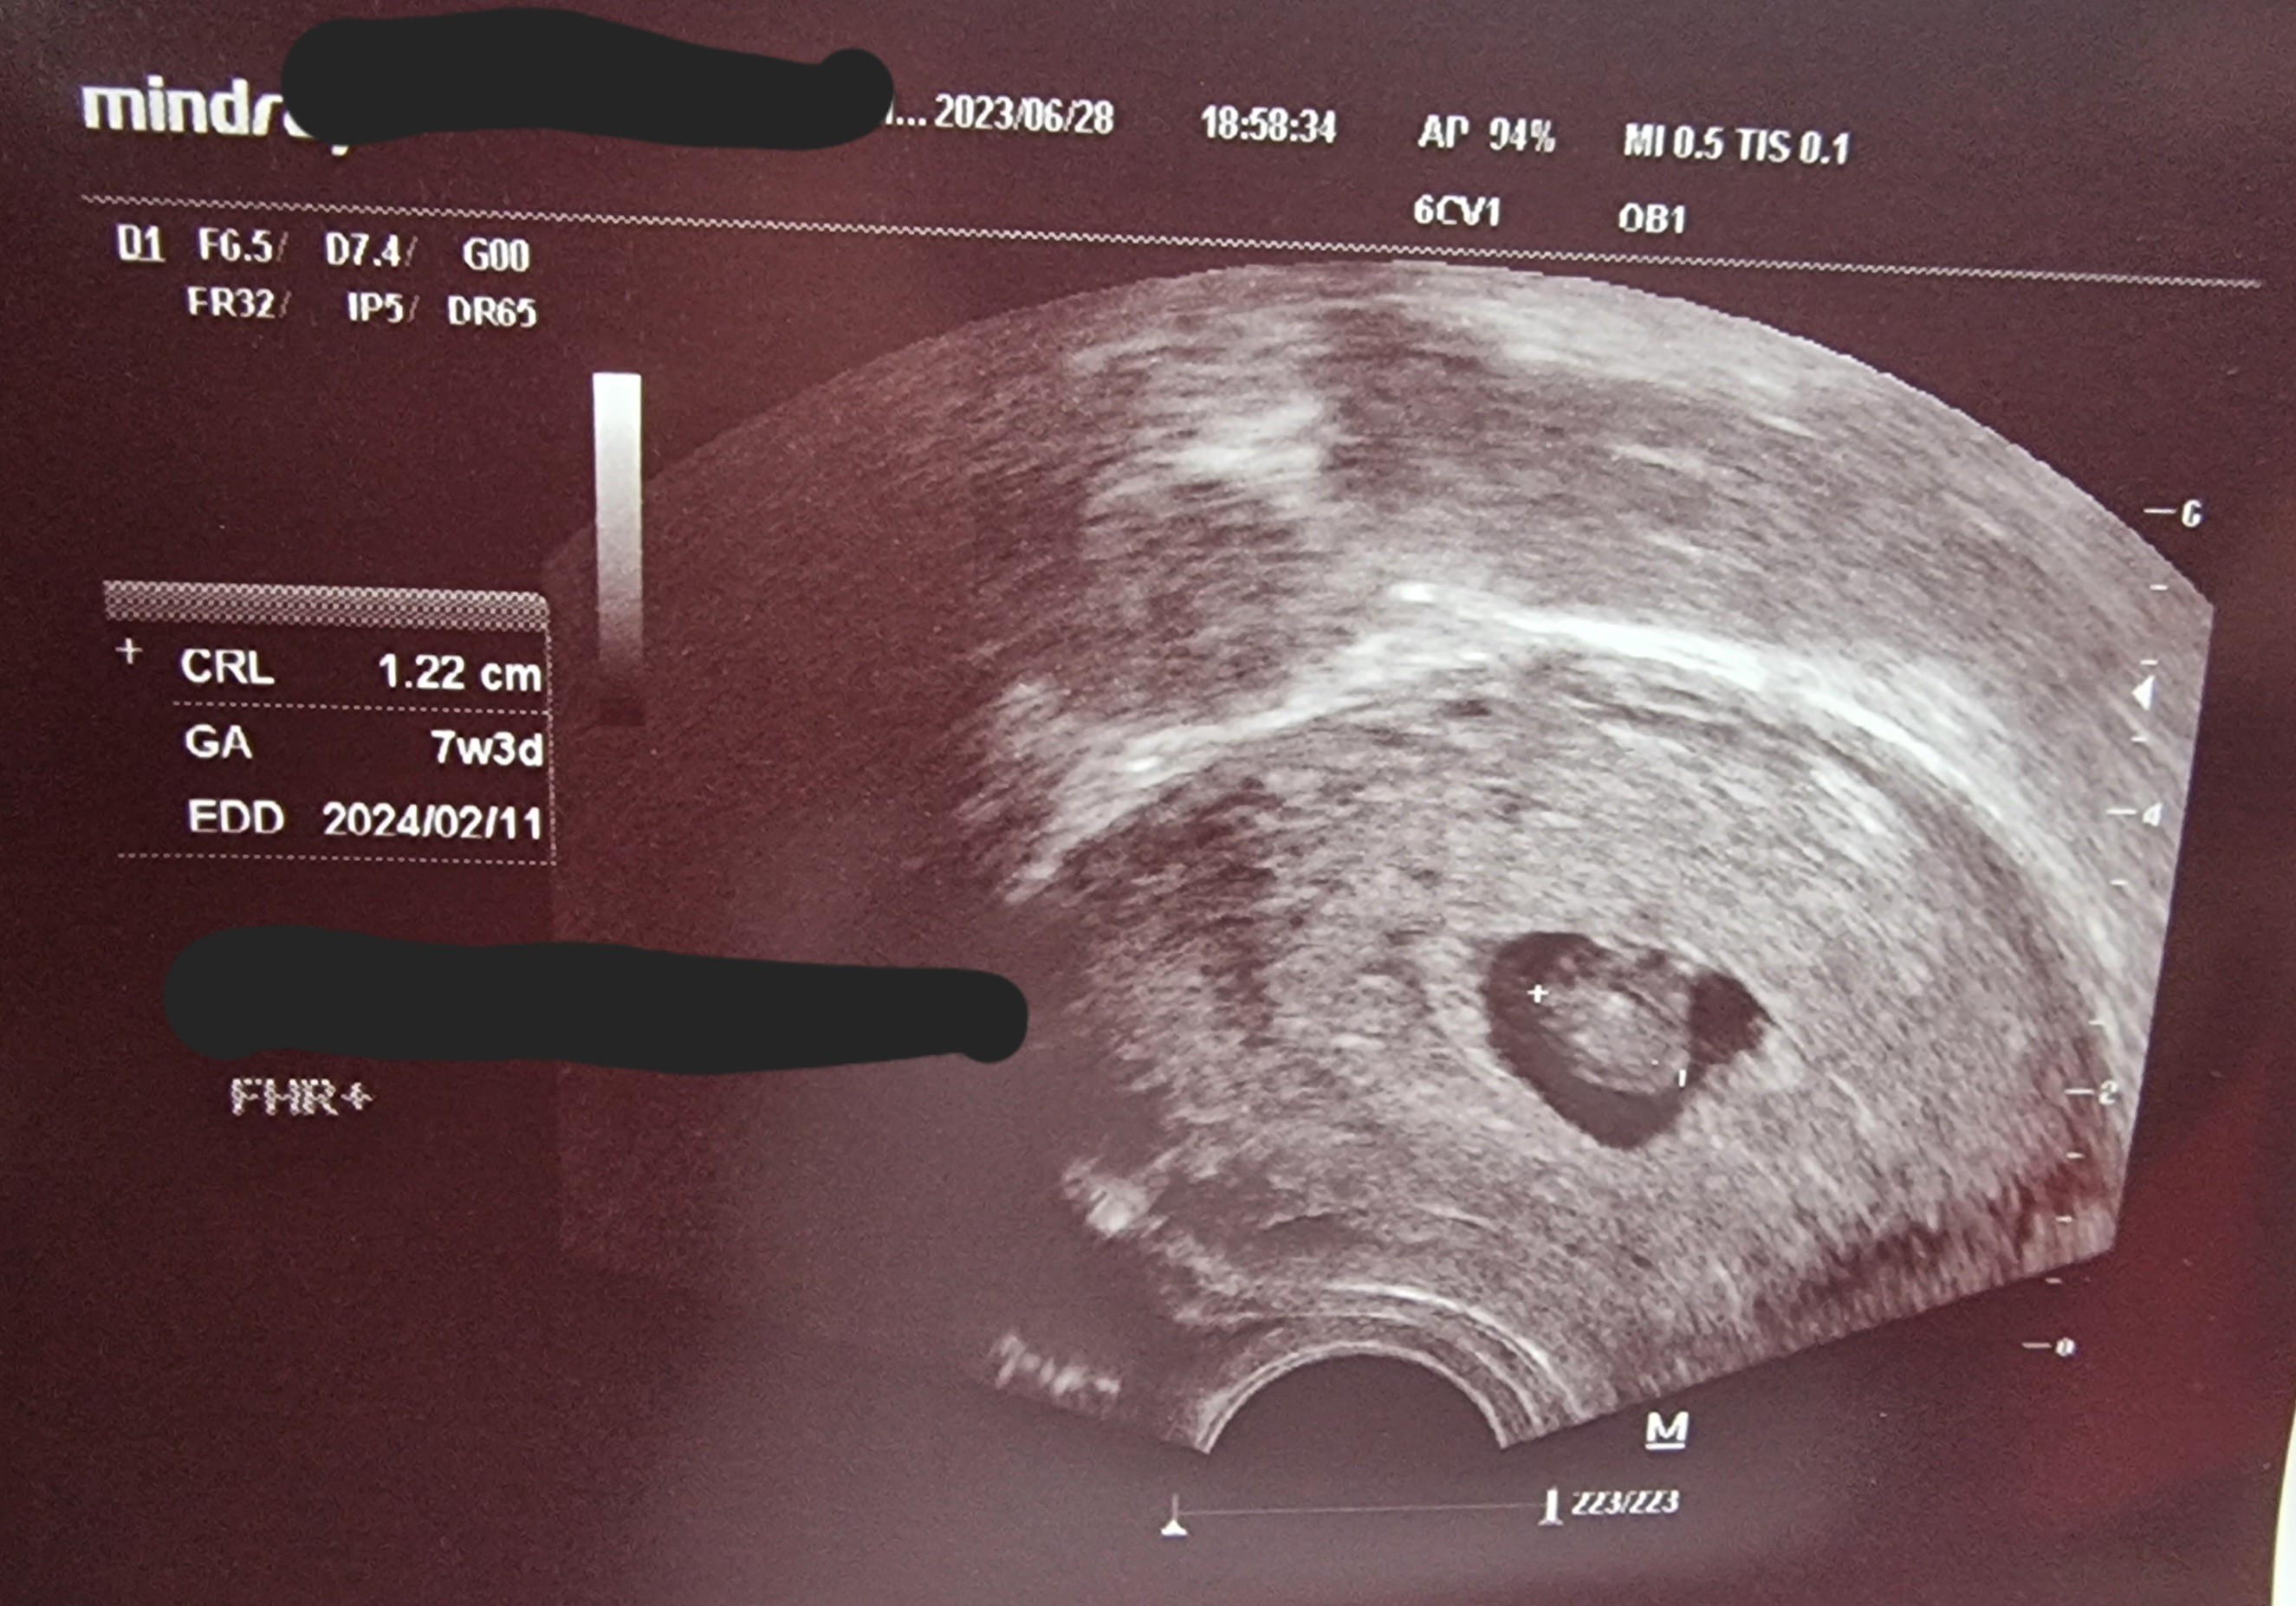

Mi się wydaje że to kwestia ujęcia, może lekarz tak ustawił by zrobić dobre pomiaryJuż pp wizycie

Na razie wydaje się, że wszystko w porządku, serduszko bije 150.

Troszkę mnie martwi tylko wygląd, w sensie mam wrażenie, że mały jest pecherzyk na ten zarodek.